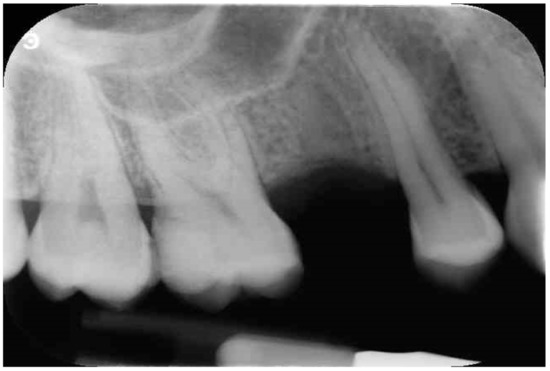

Implant Placement Following Crestal Sinus Lift with Sequential Drills and Osteotomes: Five Years after Final Loading Results from a Retrospective Study

2. Materials and Methods